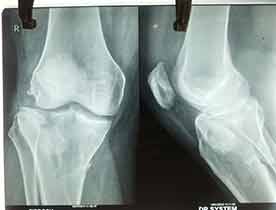

Case:1 Polytrauma Case (Multiple Fractures in Ipsilateral Limb)

Pre-Op Hip (AP & Lateral)

Pre-Op Knee (AP & Lateral)